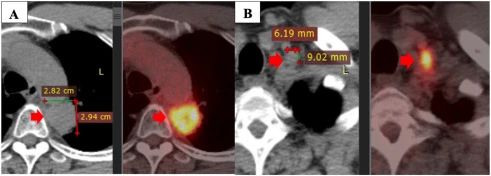

盡管如此,該疾病在 2020 年 5 月繼續(xù)發(fā)展。PET/CT 掃描顯示原發(fā)性腫瘤大小為 28×29 mm,最大標(biāo)準(zhǔn)化攝取值(SUVmax)為 11.2,粘附在縱隔胸膜和主動(dòng)脈上。此外,左側(cè)鎖骨上淋巴結(jié)的大小為 9×6 mm,左側(cè)門靜脈的一些小淋巴結(jié)大小小于 10 mm。

注:一線治療一年后疾病進(jìn)展:原發(fā)性腫瘤(A),左鎖骨上淋巴結(jié)(B)。

PD-L1 表達(dá)陽(yáng)性(25%),接受了四個(gè)周期的 Alimta(500mgx2)、卡鉑(150mgx2450mgx1)和 Cresida(4mlx2)的二線治療。然而,在 2020 年 6 月的 PET/CT 掃描中,他的病情似乎不穩(wěn)定。由于疾病的進(jìn)展,病人的治療計(jì)劃發(fā)生了變化。